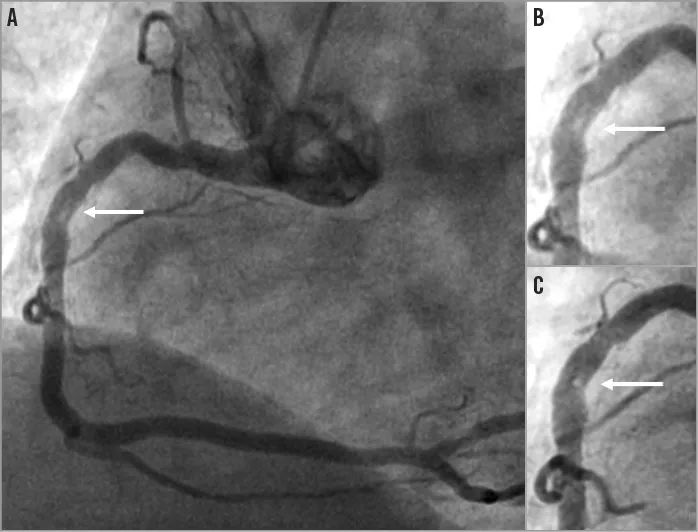

分叉病变

在分叉病变中可实现:

球囊对吻(≤4.0 NC Balloon)

球囊拘禁技术

在分支保护时可实现:

完美兼容3根导丝+1个支架或者4根导丝+一个球囊

(大腔降低导丝缠绕风险)